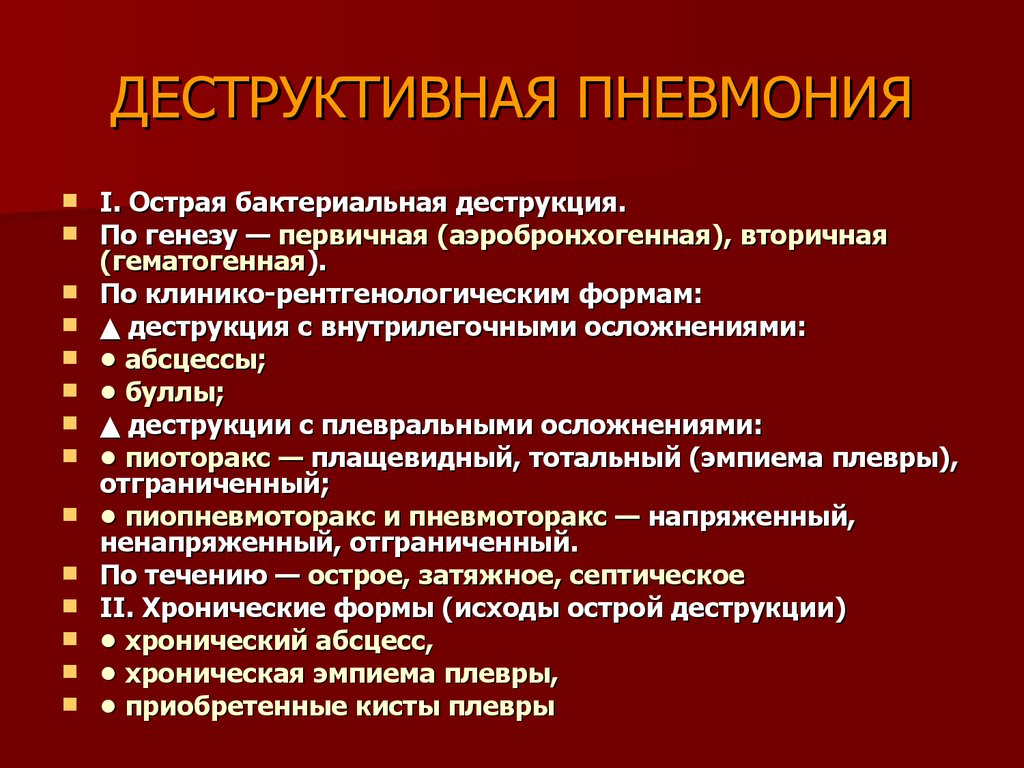

Бактериальная деструкция легких у детей презентация - 88 фото